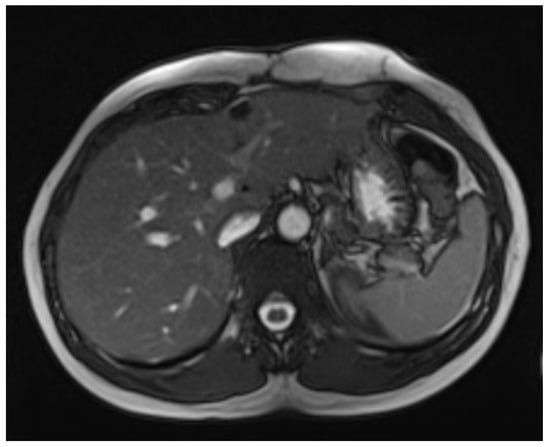

2.3. Tumor Recurrence and Further Management

3.1. Diagnosis and Imaging Characteristics